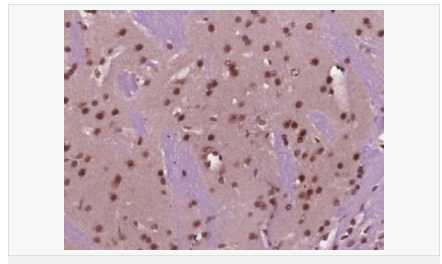

| 產(chǎn)品應(yīng)用 | WB=1:500-2000 ELISA=1:5000-10000 IHC-P=1:100-500 IHC-F=1:100-500 Flow-Cyt=1ug/test ICC=1:100 IF=1:100-500 (石蠟切片需做抗原修復(fù)) not yet tested in other applications. optimal dilutions/concentrations should be determined by the end user. |

| 細(xì)胞定位 | 細(xì)胞核 細(xì)胞漿 |